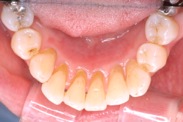

B さん

20年経過しています。下の前歯にあった歯肉の腫れも無くなり、歯周病は改善し安定しています。